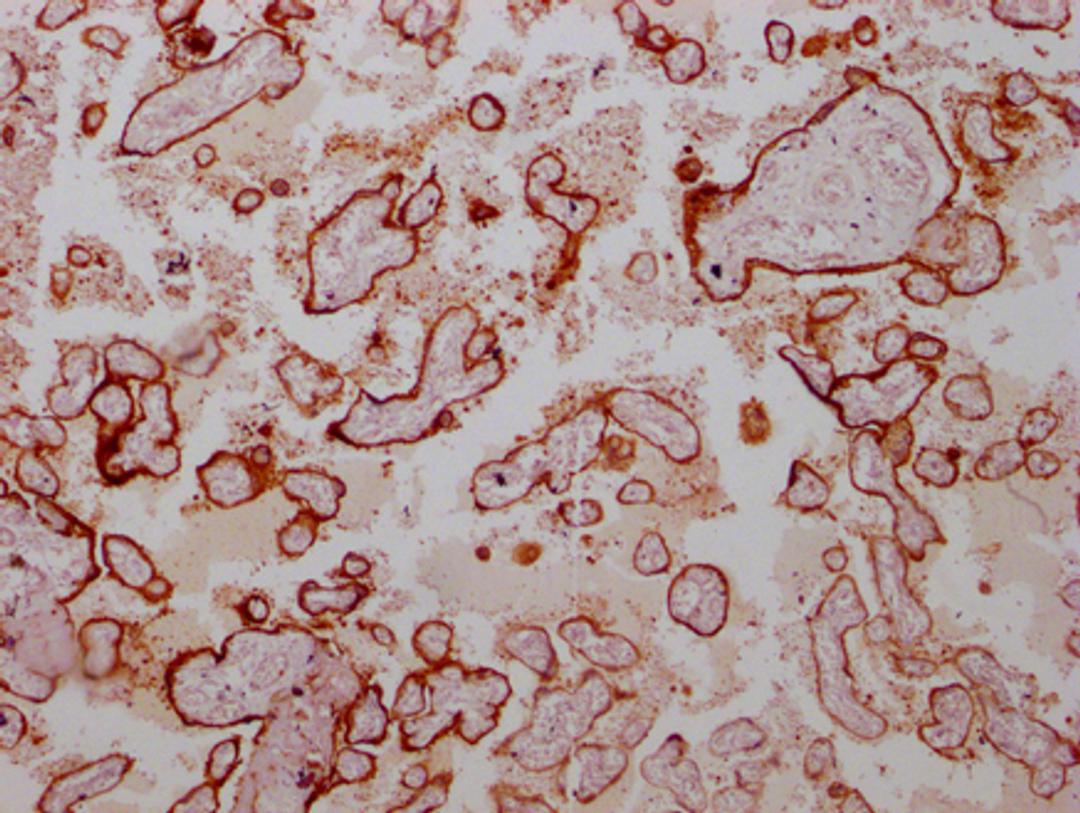

IHC image of CSB-MA219783 diluted at 1:100 and staining in paraffin-embedded human placenta tissue performed on a Leica BondTM system. After dewaxing and hydration, antigen retrieval was mediated by high pressure in a citrate buffer (pH 6.0). Section was blocked with 10% normal goat serum 30min at RT. Then primary antibody (1% BSA) was incubated at 4°C overnight. The primary is detected by a Goat anti-mouse IgG polymer labeled by HRP and visualized using 0.05% DAB.